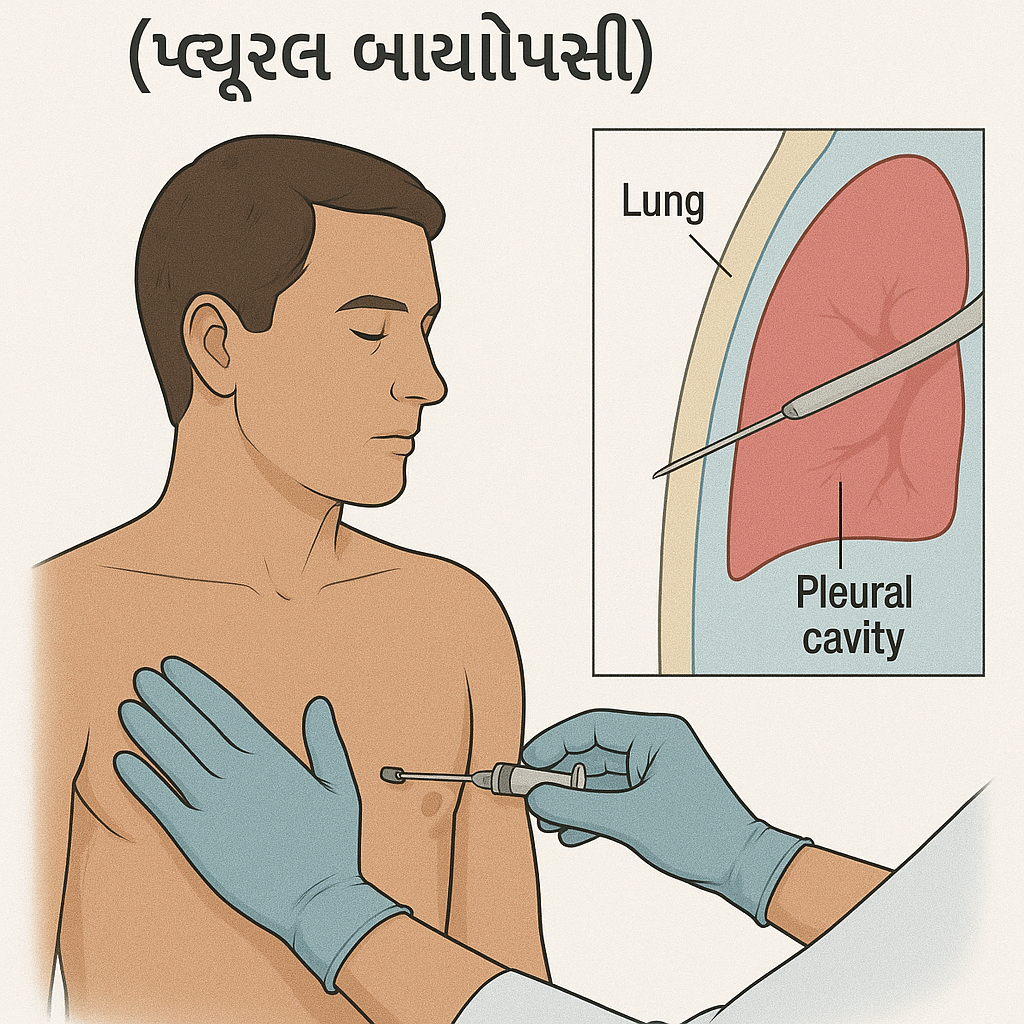

Pleural biopsy (પ્લુરલ બાયોપ્સી):

- પ્લુરલ બાયોપ્સીમાં પ્લુરામાંથી ટીસ્યુનું સ્મોલ સેમ્પલ કલેક્ટ કરવામાં આવે છે.

(લંગ અને ચેસ્ટ કેવીટીની આજુબાજુ આવેલ થીન મેમ્બ્રેનને પ્લુરા તરીકે ઓળખવામાં આવે છે). - પ્લુરલ બાયોપ્સી એ નીડલ બાયોપ્સી અથવા થોરાકોસ્કોપીની મદદથી કલેક્ટ કરવામાં આવે છે.